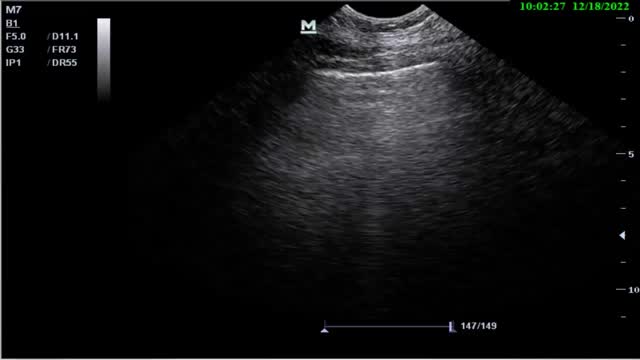

Diaphragmatic thickening and thickening fractionThe measurement of diaphragmatic thickness is another method used to determine diaphragmatic muscle mass and assess the thickening fraction (TF).27,30–32,38,39

A high-frequency linear probe is used for this measurement, positioned at the last intercostal spaces (we place the probe on the anterior axillary line, generally perpendicular to intercostal spaces 7-8, 8-9 and 9-10, with the probe covering two ribs in order to visualize the diaphragm apposition zone)(Suppl. Fig. 13), ideally with the patient in the supine position. A somewhat more posterior position of the probe has also been described, between the anterior and mid-axillary lines. In this way, we locate the “apposition zone” where the diaphragm inserts into the chest wall. The diaphragm is identified as a hypoechoic band delimited by two hyperechoic lines corresponding to the pleura and peritoneum (Suppl. Fig. 14).22,31–35

The measurement of diaphragmatic thickness is made at the end of unforced expiration. It is advisable to record at least three images for the calculation. The normality reference figures vary among the different studies.35 A study of 109 healthy individuals reported normality figures of 0.16 ± 0.04 cm, with a mean value of 0.14 ± 0.03 cm in women and 0.19 ± 0.04 cm in men (Suppl. Fig. 15).36

In contrast to thickness alone, the variation in diaphragmatic thickness during inspiration allows an indirect assessment of diaphragmatic activity. The muscle fibers shorten during contraction and cause an increase in muscle thickness. This increase during inspiration has been used as an indirect measure of contractile capacity.

The TF is the ratio between the resting thickness and the thickness in maximum inspiration. It measures the percentage increase in thickness of the diaphragm during maximum inspiration with respect to its thickness at the end of unforced expiration (Suppl. Fig. 16).30–32 At least three measurements are advised for calculating this parameter at the end of maximum inspiration and at the end of unforced or resting expiration, recording the average of both in order to calculate TF (Suppl. Fig. 16) based on the following formula30–32,34–37:

A TF of over 20-30% is considered to be normal in healthy individuals. The absence of changes in thickness during inspiration is considered to be a sensitive and specific method for diagnosing diaphragmatic paralysis.38